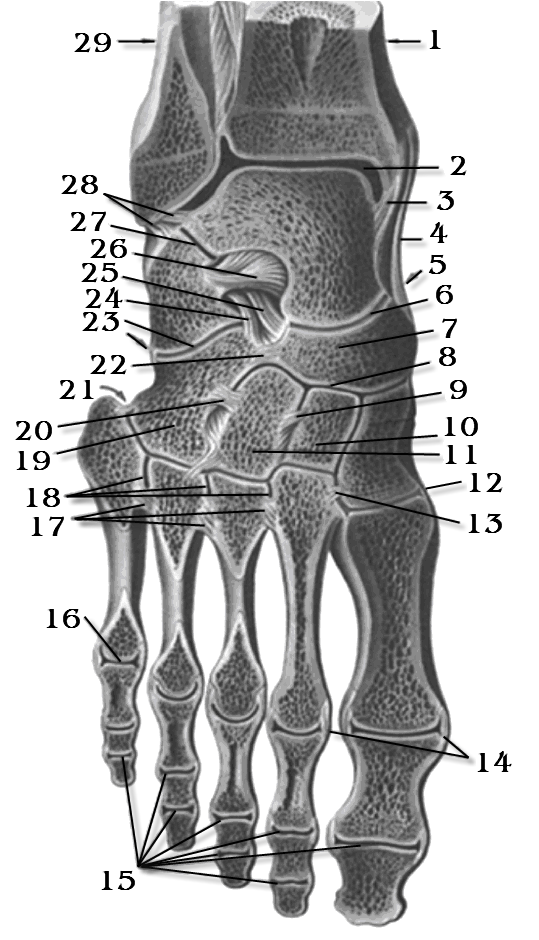

Анатомические фото голеностопного сустава и его суставных поверхностей